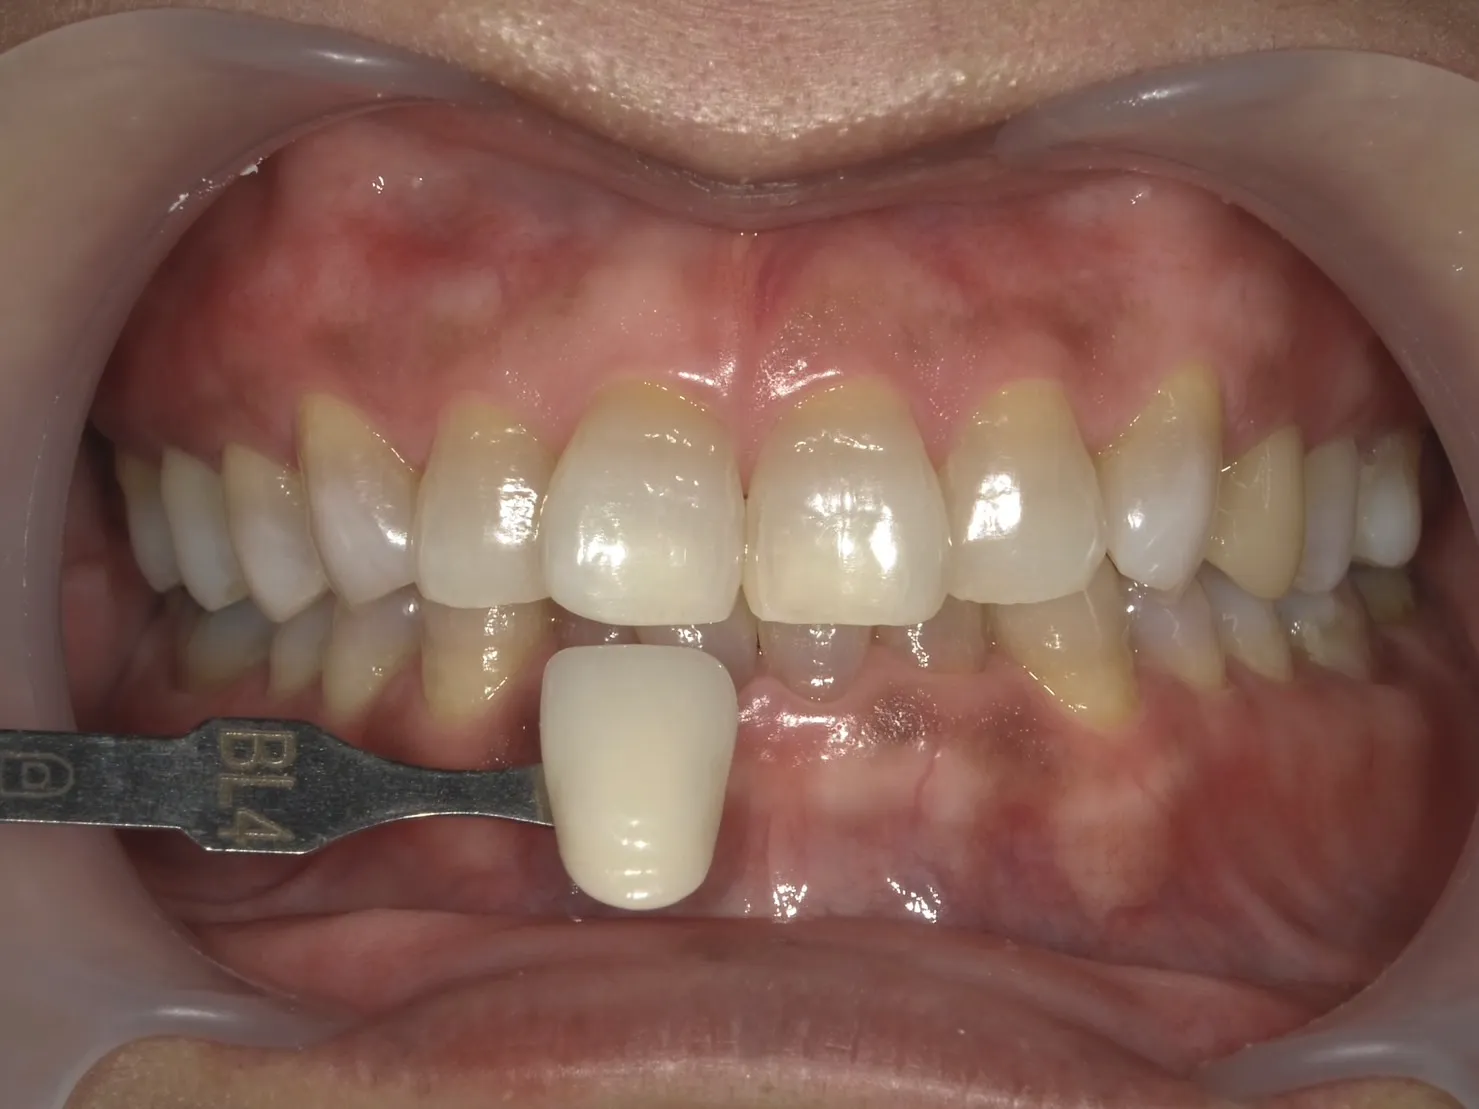

ホワイトニングは歯を削らないため、削らずに白くしてみたいという方に最適な治療法です。

特に、オフィスホワイトニングとホームホワイトニングを併用する

「デュアルホワイトニング」が効果的です。

| ホワイトニング | 非侵襲的で歯を削る必要がない 全体的に白くできる |

テトラサイクリン歯による深い着色には限界がある |